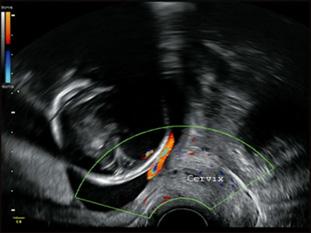

La ecografía doppler se reserva para estados fetales que muestren compromiso hemodinámico (fetos anémicos, RCIUs, gemelares monocoriales, preeclampsias, pretérminos severos), con la finalidad de detectar precozmente la insuficiencia placentaria y la hipoxia fetal. Se evalúan los siguientes vasos:

Arteria uterina

Arteria umbilical Arteria cerebral media Ductus venoso